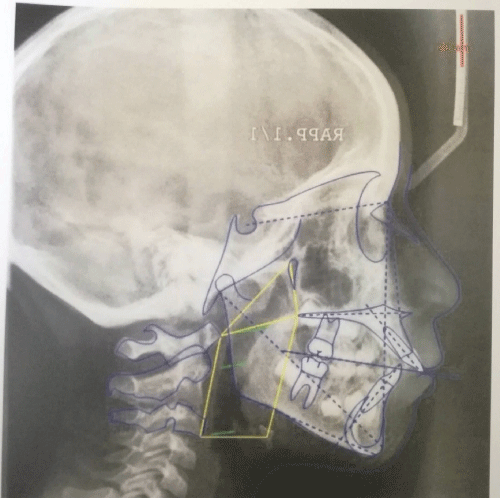

The mean age at start of treatment was 10 years while the mean age at the end was 13 years. The digital images of teleradiographs prior to treatment (T0) and subsequent treatment (T1) have been retrieved (Figure 1 and Figure 2).

Figure 1: Teleradiographs prior to treatment (T0). View Figure 1

Figure 2: Teleradiographs subsequent treatment (T1). View Figure 2

Cephalometric analysis was performed using the Delta-Dent (Outside Format) cephalometric analysis software. On our project and request was compiled by computer technicians a specific cephalometric analysis including the main parameters of the analysis of Gianni [5] and other functional parameters to describe the depth of rhino-pharyngeal and oro-pharyngeal. The other parameters are the 3 lines parallel to the SN plane passes for C1, C2, C3.